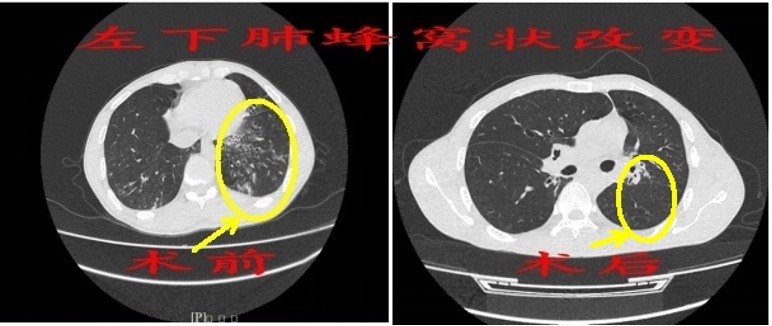

术前双侧“蜂窝”肺 术后终于消除

微创手术方案分两期实施,在2024年1月,张才铭为陈先生切除了右上 “蜂窝”肺;同年3月,二期手术切除了左下 “蜂窝”肺及左上舌段“蜂窝”肺,两次手术病理标本均证实为先天性肺囊性腺瘤样畸形(CCAM)。术后,继续加强抗感染,直至陈先生恢复良好,咳嗽咳痰症状消失,近日顺利出院。